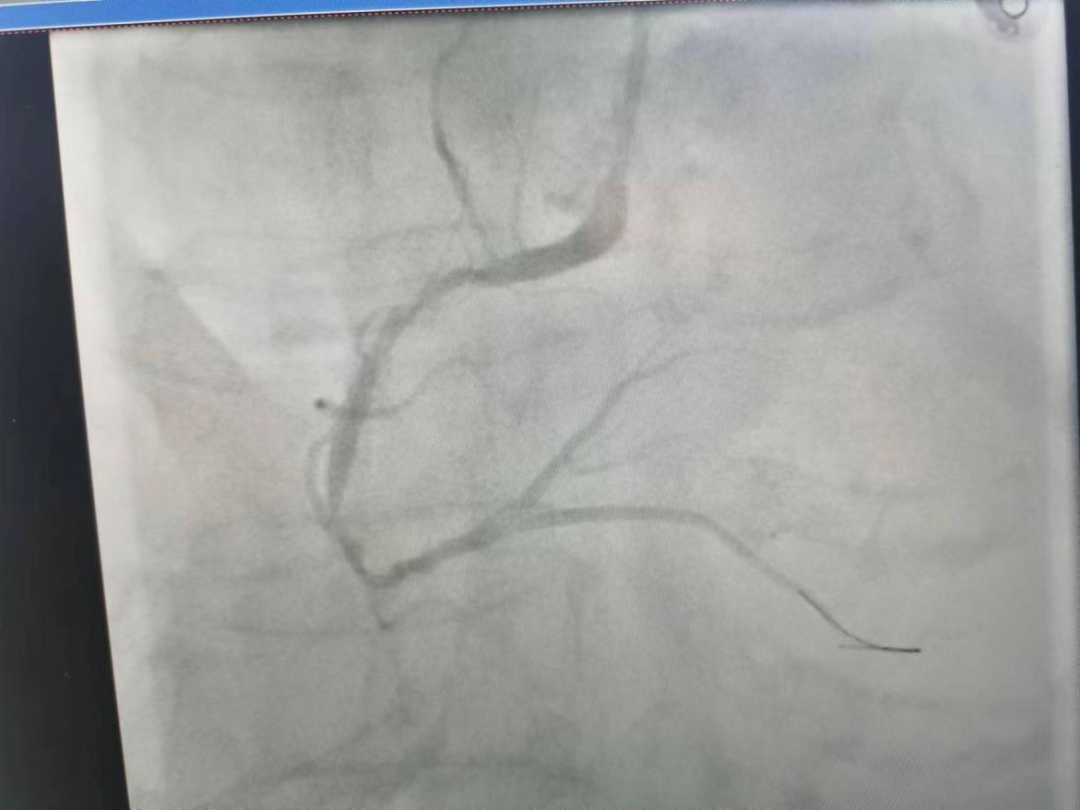

医共体总医院心血管内科治疗中发现患者后降支闭塞,予球囊扩张后返回CCU,择期处理其他血管病变,现患者病情平稳。